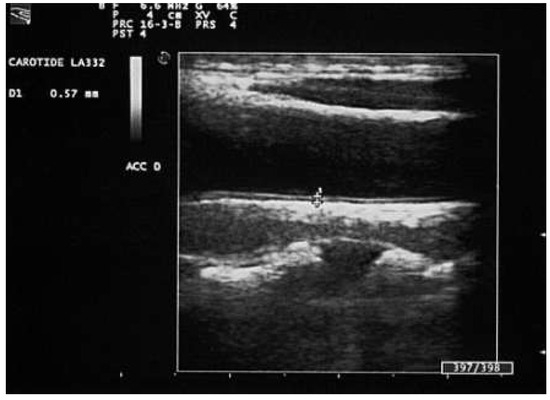

Carotid Ultrasonography in the Assessment of Cardiovascular Risk

by Aldo Pende, Nathan Artom, Giovanni Pistocchi, Livia Pisciotta and Franco Dallegri

Cardiovasc. Med. 2015, 18(2), 61; https://doi.org/10.4414/cvm.2015.00309 - 18 Feb 2015

Carotid ultrasound is one of the most accessible examinations in daily clinical practice for the evaluation of the arterial status. However, the clinical implications of the presence, the extension and the morphology of carotid damage are not entirely clear. Aim of this narrative [...] Read more.

Carotid ultrasound is one of the most accessible examinations in daily clinical practice for the evaluation of the arterial status. However, the clinical implications of the presence, the extension and the morphology of carotid damage are not entirely clear. Aim of this narrative review is to discuss the role of carotid ultrasound in the assessment of cardiovascular risk through the examination of the updated evidence in the literature. We describe the technical aspects of the procedure and the possible correlations between the imaging results and the assessment of the cardiovascular risk. Some insights about new, more sophisticated techniques for carotid evaluation, such as carotid three-dimensional and contrast-enhanced ultrasound, are also presented. Full article

Show Figures

Figure 1